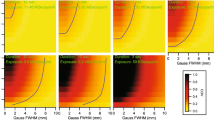

Signal-to-noise ratio

The SNR (inverse coefficient of variation) was highest for long-duration LAFOV images (10 min). Equivalency between the LAFOV and SAFOV was seen at 1.83 ± 1.00 min. The results are shown in Fig. 4.

Target lesion-to-background ratio

Improved TBR was seen on the LAFOV at 10 min (mean 2.27 ± 0.02) compared to the SAFOV (mean 2.06 ± 0.02). However, no statistically significant differences were observed for any LAFOV acquisition, even at 0.5 min, p = 0.47), suggesting adequate lesion-to-background contrast even for short acquisitions. The results are shown in Fig. 5.

Image quality

All MIP and axial images (10, 4, 2, 1, 0.5 min LAFOV and full acquisition SAFOV) were ranked at blinded assessment in order of quality. The readers were unaware of the scanner type, scan order or clinical details and had not previously seen these cases. The reference SAFOV images were consistently ranked as of inferior quality, with a median ranking of 4th worst (range 3–5), and were largely evaluated as intermediate between the 2 and 0.5 min LAFOV images. Overall image quality on the LAFOV correlated with length of acquisition, with the 10 min being ranked as highest quality in 100% of the cases. The average scan times for the LAFOV ranked as equivalent to the SAFOV reference acquisitions were as follows: 18F-FDG 1.95 ± 0.86 min, 18F-PSMA-1007 1.95 ± 0.86 min, 68Ga-DOTA-TOC 1.50 ± 0.48 min. Image quality for the LAFOV correlated perfectly with length of acquisition time for all radiotracers (Pearson’s rank coefficient 0.997 for 18F-FDG, 1 for 18F-PSMA-1007 and 68Ga-DOTA-TOC). Example images are presented in Fig. 6.